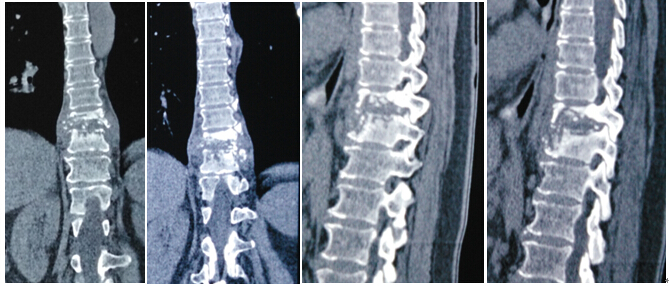

2016年4月29日我科应用椎间孔镜技术、经皮椎弓根螺钉技术成功治疗1例胸椎结核病例。患者女性,67岁,因“胸背部疼痛2月余,加重1月”就诊,经门诊就诊后积极抗结核治疗3周住院治疗。入院患者胸背部疼痛明显,CT示T10、T11椎体骨质破坏,T10塌陷。经科室讨论后应用经皮椎间孔镜技术经椎间孔入路行病灶清除、颗粒骨植骨,再经后路经皮椎弓根螺钉固定。手术顺利,无并发症,目前患者病情平稳。

术前影像学资料